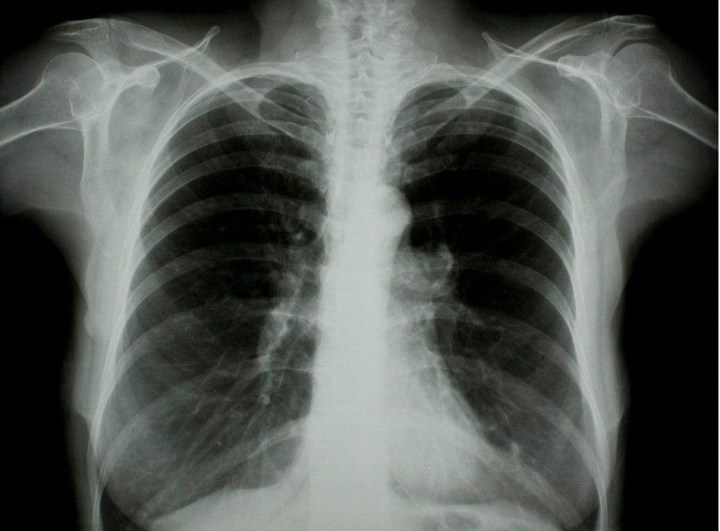

摘要:新冠肺炎最新癥狀包括發(fā)熱、咳嗽、乏力、呼吸急促等。了解這些癥狀對(duì)于預(yù)防和控制疫情至關(guān)重要。預(yù)防策略包括戴口罩、勤洗手、保持社交距離等。應(yīng)對(duì)策略包括及時(shí)就醫(yī)、隔離觀察、接受治療和遵循醫(yī)生建議。了解這些信息有助于公眾更好地應(yīng)對(duì)新冠肺炎疫情。

新冠肺炎(COVID-19)自爆發(fā)以來,全球范圍內(nèi)都在密切關(guān)注其動(dòng)態(tài),隨著病毒的不斷變異,其癥狀表現(xiàn)也可能有所變化,本文將對(duì)新冠肺炎最新癥狀進(jìn)行詳細(xì)介紹,幫助公眾更好地了解與應(yīng)對(duì)這一疫情。

根據(jù)最新的醫(yī)學(xué)研究和報(bào)道,新冠肺炎的癥狀表現(xiàn)多樣,主要包括發(fā)熱、干咳、乏力等典型癥狀,以及一系列新發(fā)現(xiàn)的癥狀,這些癥狀有助于醫(yī)生更早地發(fā)現(xiàn)病例并采取相應(yīng)措施。

5、呼吸急促:隨著病情發(fā)展,患者可能出現(xiàn)呼吸急促、呼吸困難等癥狀。

8、胸痛:少數(shù)患者可能出現(xiàn)胸痛癥狀,可能與肺部炎癥有關(guān)。